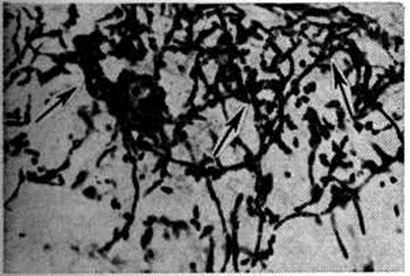

Кандидоз кожи проявляется в виде подострых дерматитов в складках кожи, изредка с образованием абсцессов и изъязвлением. При гистологический исследовании отмечается межклеточный отёк эпидермиса, паракератоз, акантоз и прорастание нитей грибка в некротизированный эпидермис (рисунок 2). Воспалительная инфильтрация преимущественно из сегментоядерных лейкоцитов наблюдается в основном в дерме. Иногда наблюдается формирование ограниченных абсцессов с наличием распадающихся сегментоядерных лейкоцитов. Впоследствии образуются гранулемы, состоящие из лимфоцитов, эпителиоидных и гигантских клеток (рисунок 3).

Рис. 3. | ||

Гистологический картина изменений в метастатических очагах различных органов и тканей не имеет строго выраженных специфических черт. В начальной стадии кандидозного процесса наблюдается некротически-экссудативная воспалительная реакция, чаще гнойного характера, реже с преобладанием в инфильтрате лимфоцитов. Интенсивность разрастания грибка зависит от жизнеспособности ткани: там, где некроз выражен резче, нитей грибка значительно больше. При хронический течении процесса вокруг некротически-экссудативного очага воспаления происходит разрастание соединительной ткани или наблюдается формирование гранулемы (смотри полный свод знаний), напоминающей таковую при туберкулёзе (рисунок 3). Ликвидация грибка в организме происходит в основном за счёт лизосомальных ферментов сегментоядерных лейкоцитов (рисунок 4), то есть в результате так называемый внеклеточного фагоцитоза, поэтому рост грибка в гнойном очаге обычно тормозится. Присутствие большого количества сегментоядерных лейкоцитов препятствует размножению грибка, лейкоциты как бы облепляют элементы грибка и, подвергаясь распаду, отграничивают его от окружающей ткани (рисунок 5). Как показывают электронно-микроскопические исследования, в клетках грибка нарушается целостность цитоплазматической мембраны и появляются аутофагические вакуоли в цитоплазме. Фагоцитоз грибков сегментоядерными лейкоцитами встречается редко и касается в основном нежизнеспособных клеток грибков; в цитоплазме же макрофагов (рисунок 6) и гигантских клеток грибок может находиться длительное время и быть жизнеспособным — так называемый эндоцитобиоз. Поскольку грибок способен к внутриклеточному паразитированию, то наличие его жизнеспособных форм свидетельствует о том, что воспалительный процесс имеет затяжной характер.